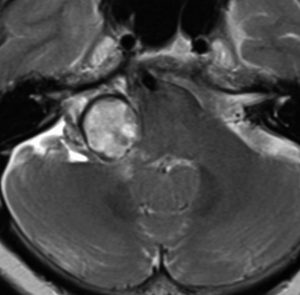

何も考えないで手術しなければならない時

聴神経腫瘍でまず手術が必要なのは巨大なものです。この4枚の写真は私が実際に手術をした患者さんのものです。脳幹部という脳の最も大切なところが腫瘍によって圧迫されて変形しているのが特徴です。右上のものはのう胞性腫瘍なので大きさの割に手術のリスクは高くありませんが,左上のものは実質性で出血性のものですごくリスクが高い手術でした。左下のものは普通のリスク。右下のものは超高難易度のものです。

この腫瘍は脳幹部変形がとても強く,大きいので手術摘出するしか選択肢はありません

- 脳幹部の変形が高度な大きな腫瘍になると手術するしかありません

- 4cmを超えると危険だと考えてください

- のう胞性(腫瘍の内部がほとんど液体)のものは4cmを超えても手術は危なくないです

- 巨大な充実性の聴神経腫瘍の手術では命をなくすリスクもあるものです